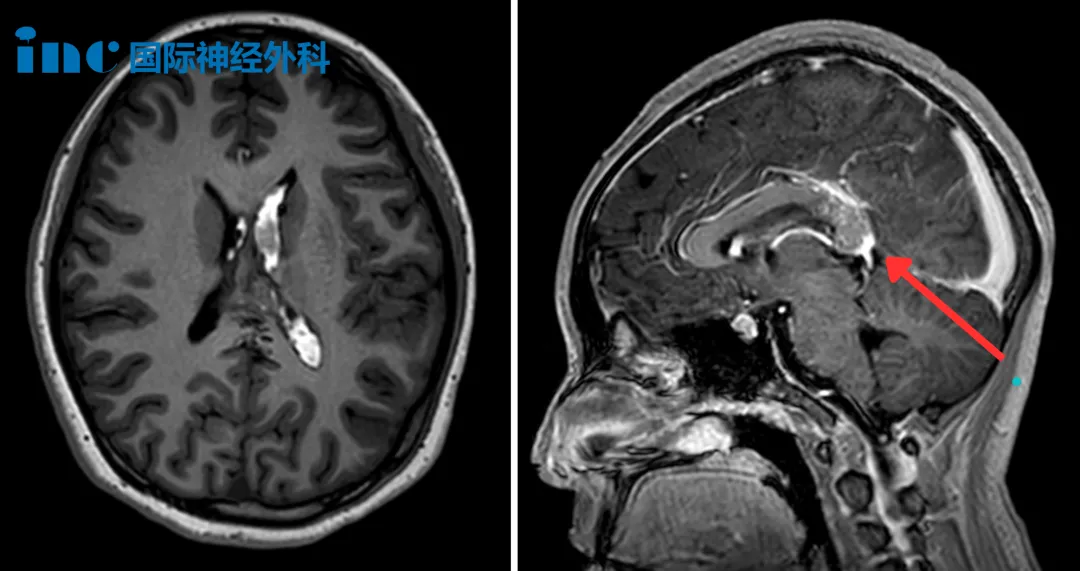

三天后,医生拔除了右侧引流管,仅保留左侧继续引流脑脊液。可当日的头颅MRI检查,却揭开了更棘手的真相:在大脑深处的胼胝体压部,藏着一个22mm×15mm的橄榄形病灶——脑动静脉畸形(AVM)。

诊室里,巴教授拿着小蕊的MRI影像,逐帧细致分析:“孩子的AVM仍然有可能再次出血,因为有很多小的AVM血管,这些血管很脆弱,所以可能会再次破裂。”当小蕊父母颤抖着问能否手术?巴教授的回答给了他们定心丸:“这确实不是一台容易的手术,但非常可行。”